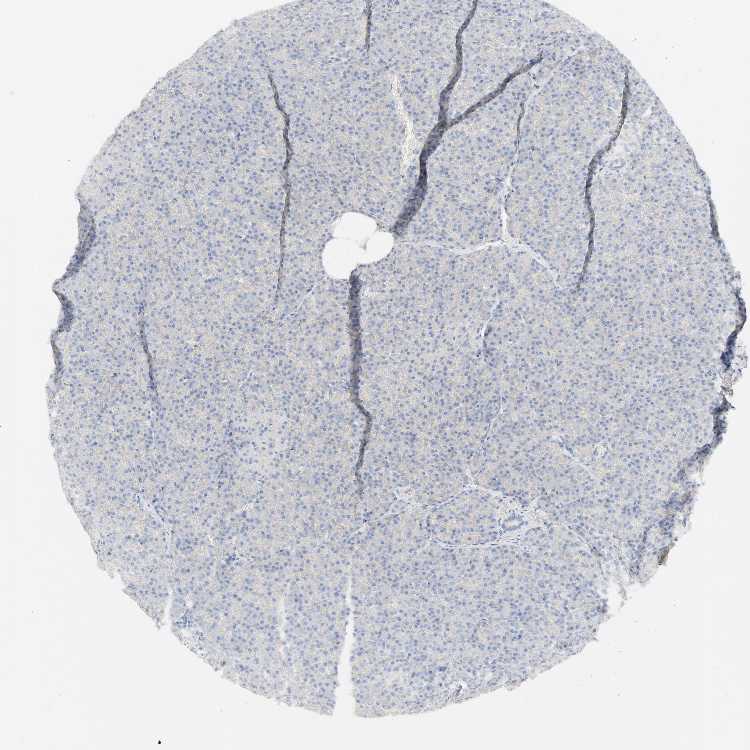

PANCREAS - Antibody stainingi

Antibody staining in the annotated cell types in the current human tissue is reported as not detected, low, medium, or high, based on conventional immunohistochemistry profiling in selected tissues. This score is based on the combination of the staining intensity and fraction of stained cells.

Each image is clickable and will lead to virtual microscopy that enables deeper exploration of all samples and also displays staining intensity scores, fraction scores and subcellular localization as well as patient and tissue information for each sample.

Antibody HPA004338

Exocrine glandular cells Not detected

Pancreatic endocrine cells Not detected